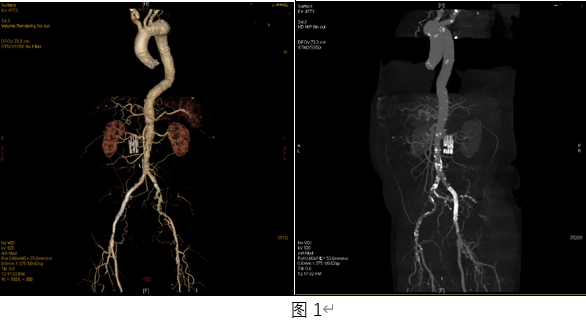

术前CTA检查提示,该患者全身动脉血管多处病变(图1),其中左侧髂动脉严重钙化狭窄(图2),不仅是患者左下肢跛行的“元凶”,也会成为主动脉瘤微创介入治疗的“拦路虎”,如此坚硬的钙化病变,手术操作风险高、难度大。经手术团队反复研判,决定引入国际先进的Shockwave外周血管内冲击波治疗技术,该技术通过脉冲发放血管内冲击波,“隔山打牛”般作用于钙化病变,使得斑块重塑,血流恢复通畅、血管恢复柔顺,能够最大限度恢复血管正常生理功能。